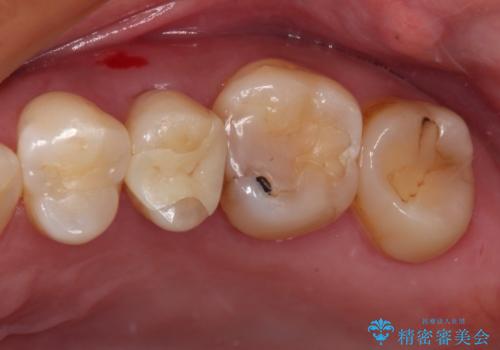

目立つ銀歯と欠けてしまった詰め物 オールセラミッククラウンでの補綴治療

不快感の強い奥歯 オールセラミッククラウンでのむし歯治療

痛みでうずく 根管治療と補綴治療